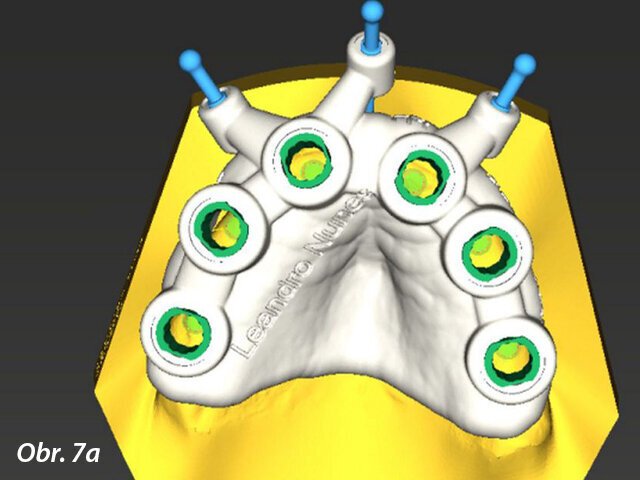

Prostřednictvím softwaru coDiagnostiX jsme zjistili, že je k dispozici dostatek kosti pro zavedení implantátů, kromě dvou oblastí, do nichž bude nutno transplantovat kostní štěp (obr. 5, 6). Bylo naplánováno celkem šest implantátů s adekvátním rozložením po oblouku, které vytvoří podpěru pro žvýkací síly a zabrání jednostranné zátěži (obr. 7). Zavedení implantátů bylo naplánováno za použití chirurgické šablony (obr. 8) a na implantáty měla být hned po chirurgickém zákroku našroubována provizorní náhrada – jednalo se tedy o protokol okamžitého zatížení.